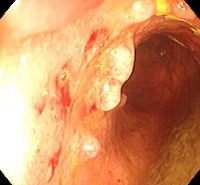

Диагноз устанавливается на основании эндоскопических исследований. В процессе ректороманоскопии или колоноскопии врач изучает состояние слизистой, выявляет изъязвления и другие изменения, характерные для неспецифического язвенного колита и других заболеваний, способных спровоцировать псевдополипоз ободочной кишки. Эндоскопист оценивает количество, размер и форму псевдополипов, берет образцы ткани узлов и соседних участков слизистой оболочки для морфологического исследования.

В процессе изучения морфологической структуры образований, возникающих у больных псевдополипозом ободочной кишки, определяется неизмененный эпителий, разрастания эпителия или грануляционная ткань. При исследовании слизистой оболочки, пораженной язвенным колитом выявляются расширенные капилляры, кровоизлияния, язвы и крипт-абсцессы. Подслизистый слой обычно изменен незначительно. Слизистая оболочка кишечника у пациентов с болезнью Крона грубая, бугристая, по внешнему виду напоминает «булыжную мостовую».